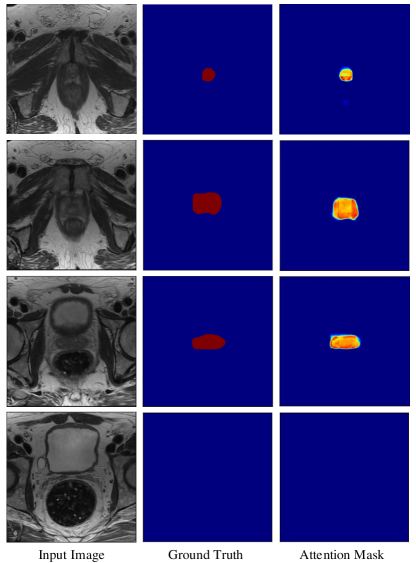

Refer to caption

Figure 9: Attention mask examples produced by the attention-focused module. The blue, red pixel represents background and prostate, respectively. And the attention mask is the corresponding heat map produced by attention-focused modules. For the heat map, the darker the color, the greater the weight value, the lighter the color, the smaller the weight value.

5.2 Analysis of Attention-focused Modules

To further analyze the function of attention-focused modules, we visualized the generated attention masks in the up-sampling path. Four different types of input images were selected, which are selected from base, mid-gland, apex and also outside of the prostate. It can be seen that the attention masks have much higher weights in the prostate region than in the non-prostate region as shown in Fig. 9. And the shape of attention mask was very close to the ground truth. It is conceivable that higher weight was inside the attention masks, which helps to locate the region of prostate. The shape of the attention mask volume was again close to the ground truth. It suggests that the attention mask can help the network pay more attention to the region of prostate and suppress the features from the non-prostate region towards better image segmentation.